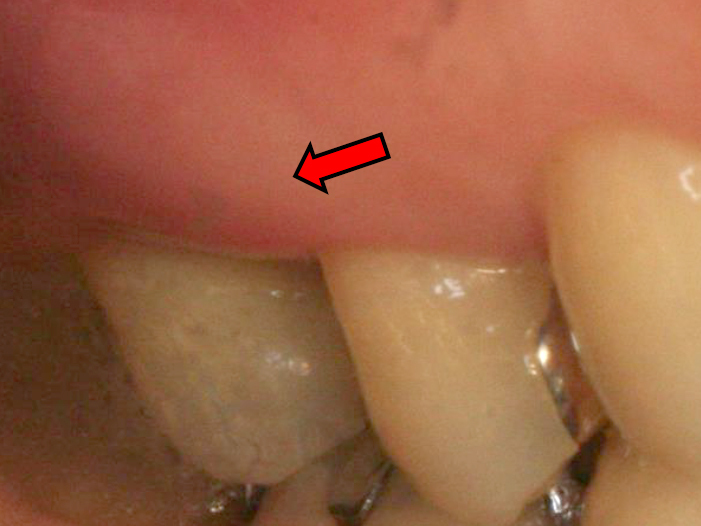

歯周基本治療・歯周外科処置を行なった症例

歯周基本治療後

歯周外科処置

初診時年齢:30代女性

治療:歯周病治療

治療法:歯周基本治療、歯周外科処置

治療期間:1年6ヶ月

費用:保険診療

リスク・副作用:歯周外科処置後に出血、腫れ、あざが出ることがありますが時間とともに治ります。術後3週間程度噛んだときの痛みや歯が浮いた感じがすることがあります。術後の歯肉退縮により知覚過敏が生じることがあります、時間とともに落ち着くこともありますが症状が続く場合は根管治療を行います。